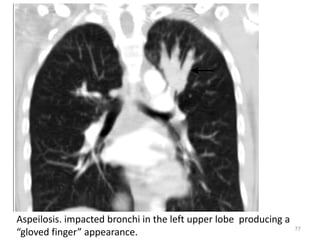

Aspeilosis. impacted bronchi in the left upper lobe producing a

“gloved finger” appearance.